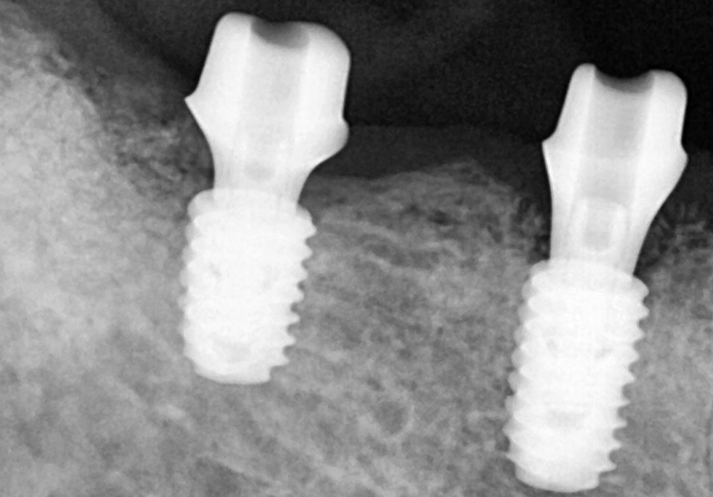

We waited 충분히 long so that the implant could be well fixed in the jawbone,

![[Seokchon Gobun Station Dental Clinic] When Is an Implant Needed? image 6](https://pub-9f2bb3498faf4d1d8714b41df24753e3.r2.dev/content/clinics/archive/2yawovf9te/naver_blog/qkrgnsdms66403/assets/by_hash/b57510d3c14833982a2fc39f3d71d9a77fe733bb2d292ef5af5631d2cc94fd2d.png)

This shows the custom abutment being attached

for the crown (prosthesis) work.